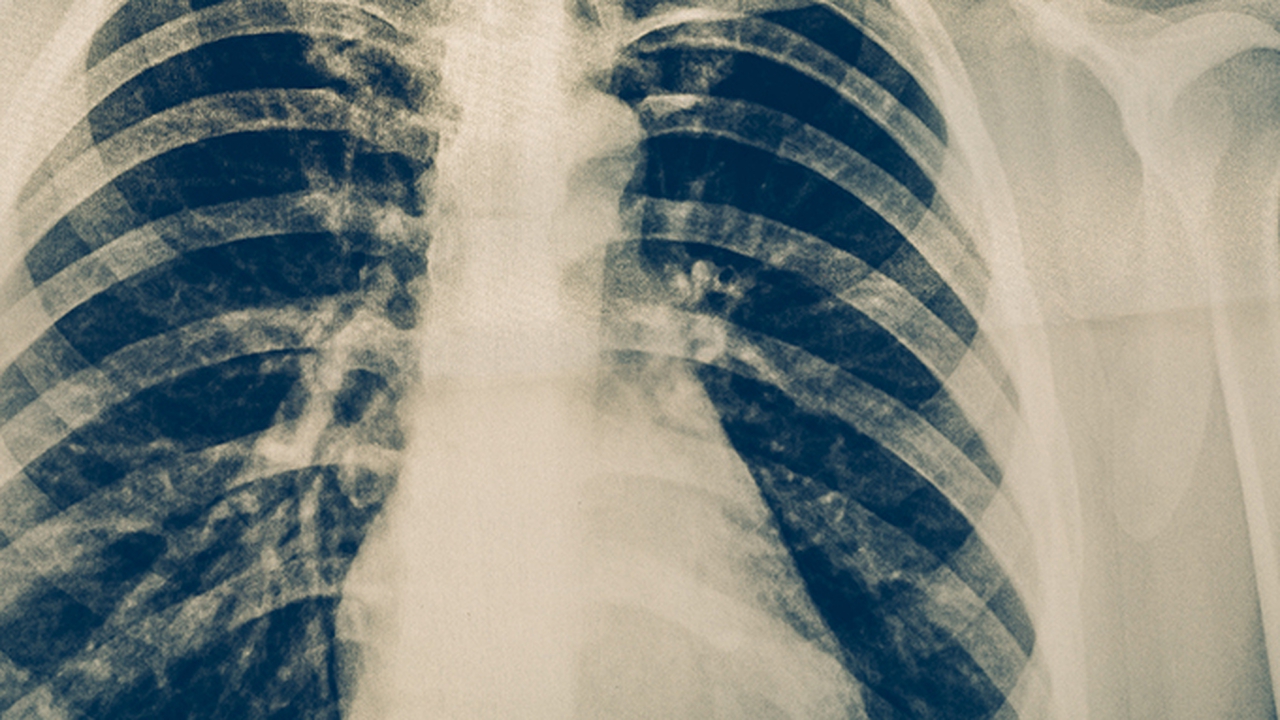

肺癌是一种常见的恶性肿瘤,其发病原因复杂,包括吸烟、环境污染、职业暴露等多种因素。早期诊断和规范治疗对提高患者生存率至关重要。目前,肺癌的治疗方法主要包括手术、放疗、化疗、靶向治疗和免疫治疗等。